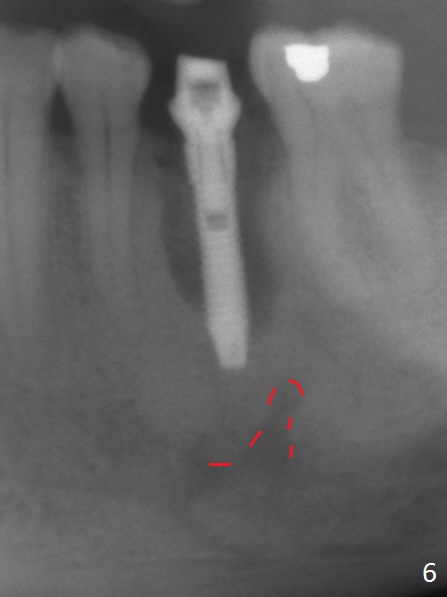

Extraction of the lower left 2nd premolar with vertical fracture (Fig.1,2 >) is easy because of peri-radicular radiolucency.  The apical end of the osteotomy is not shown with a 2 mm pilot drill (Fig.3) or a 3.8x18 mm implant (Fig.4) in place.  It appears that the implant is not placed deep enough.  Following 3-4 more turns of the implant and placement of a 5.5x4(3) mm abutment (Fig.5 A), allograft is placed (*).  A postop panoramic X-ray is taken (Fig.6); the osteotomy could have been deepened to reduce the possibility of periimplantitis.  Retrospectively, the panoramic X-ray should be taken after use of the pilot drill. The bone around the implant appears to have regenerated 4 months postop (Fig.7,8).  Bone density appears to continue increasing 9 months postop (i.e., 4.5 months post cementation, Fig.9).  Bone loss is minimal 2 years post cementation (Fig.10).